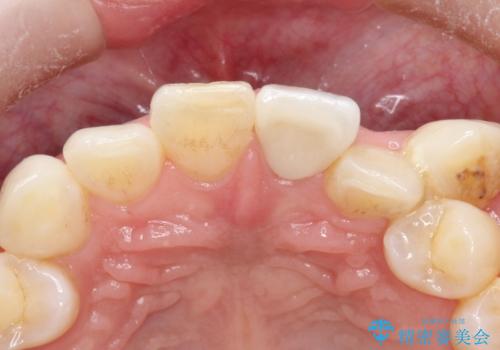

前歯を綺麗にしたい オールセラミッククラウン

- 他院で前歯の変色をダイレクトボンディングにて修復治療しておりましたが、審美障害を主訴に来院されました。

根管治療後、オールセラミックにて治療を行っております。

ダイレクトボンディングはセラミックに比べ経年劣化しやすい材料です。

今回はオールセラミッククラウンによる治療を行いより審美的な修復ができました。